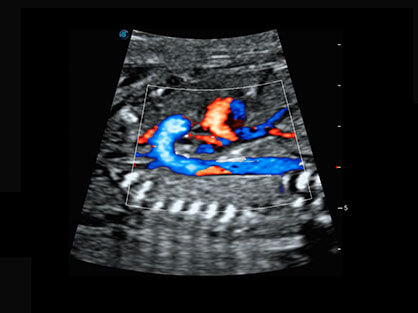

通过对组织运动信息、血流信号及背景噪声进行准确智能的阈值判定,高效提取出微弱血流信号,获得高灵敏度和空间分辨率的血流图像,为临床提供更加真实和丰富的诊断信息。

宽频带腹部凸阵探头和腹部容积探头、大角度腔内探头和腔内容积探头、独特的生殖专用曲柄探头,为妇产应用提供全面诊疗方案。